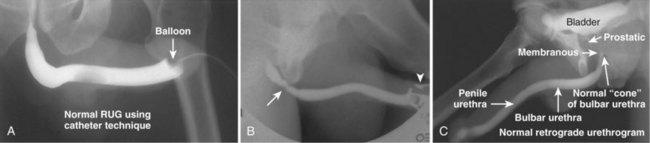

A retrograde urethrogram is a study meant to evaluate the anterior and posterior urethra. Retrograde urethrography may be particularly beneficial in demonstrating the total length of a urethral stricture, which cannot be negotiated by cystoscopy. Retrograde urethrography also demonstrates the anatomy of the urethra distal to a stricture, which may not be assessable by voiding cystourethrography. Retrograde urethrography may be performed in the office or in the operating room before performing visual internal urethrotomy or formal urethroplasty.

A plain film radiograph is obtained before injection of contrast. The patient is usually positioned slightly obliquely to allow evaluation of the full length of urethra. The penis is placed on slight tension. A small catheter may be inserted into the fossa navicularis with the balloon inflated to 2 mL with sterile water. Contrast is then introduced via catheter-tipped syringe. Alternatively, a penile clamp (e.g., Brodney clamp) may be used to occlude the urethra around the catheter (Fig. 4–9).